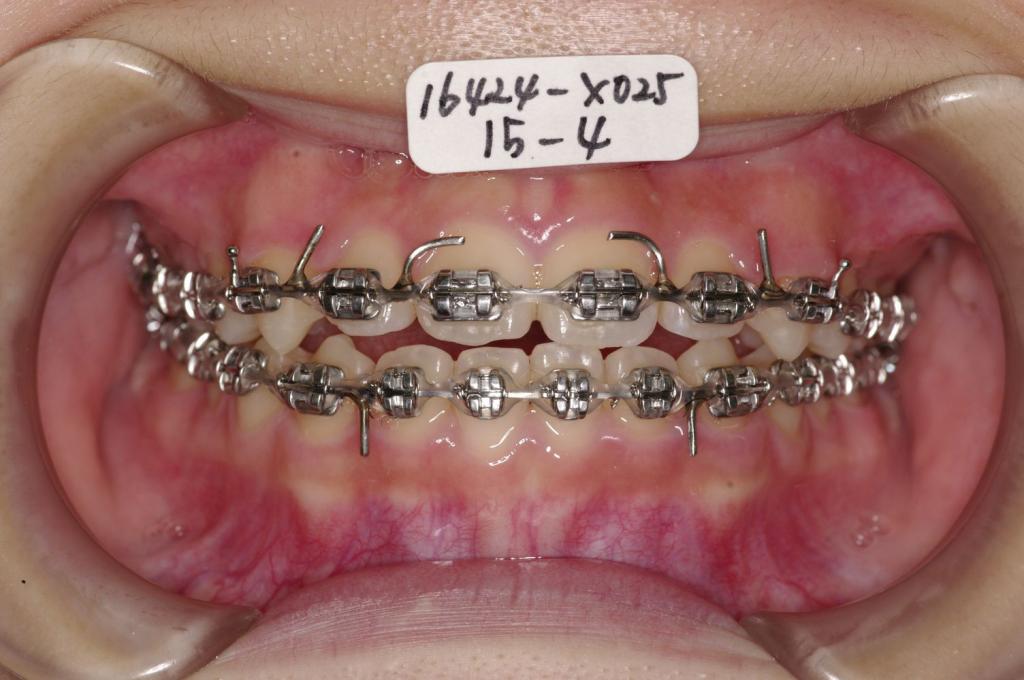

装置写真

治療前

前歯、出っ歯・開咬の矯正治療前口内写真NO.1095

治療後

前歯、出っ歯・開咬の矯正治療後口内写真NO.1095

装置の種類及び治療法 診断:叢生 上下顎前突

治療方法および装置:マルチブラケット装置

High pull J-hook headgear

抜歯:非抜歯

治療期間:11ヶ月